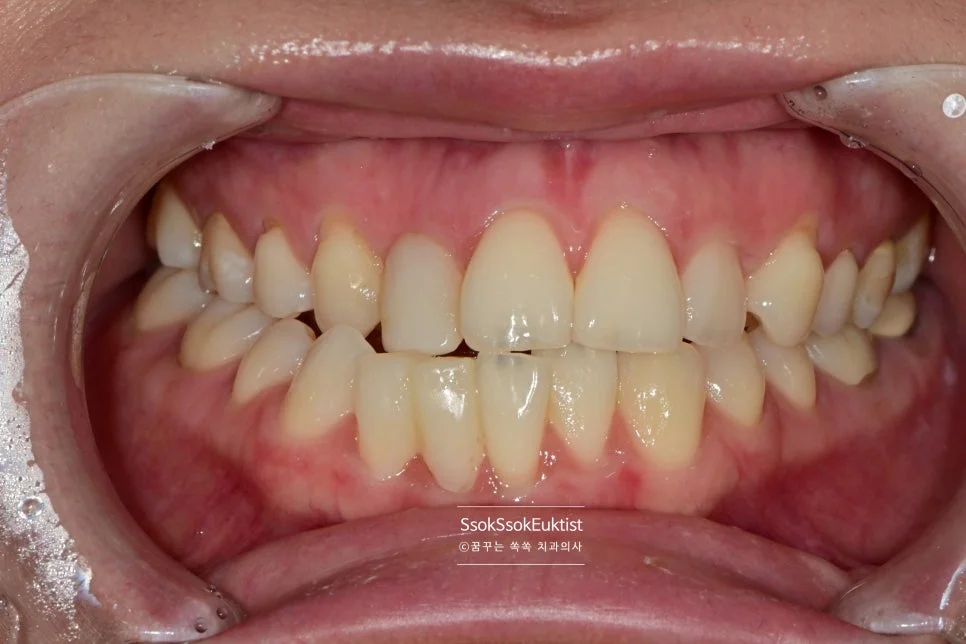

치료 전 정면 교합 사진 — 아래 앞니의 배열 상태 확인

진단 사진 — 가지런하지 않고 정출된 치아, 레진 치료가 되어 있는 부위 (화살표)

아래 앞니의 모양 개선을 원하는 증례입니다.

사진상에서 왼쪽(환자분의 오른쪽) 앞니 두 개가 주변 치아 대비 살짝 솟아 있는 것, 그리고 가지런하지 않은 모양이 내심 오랫동안 마음에 쓰이셨던 것 같습니다.